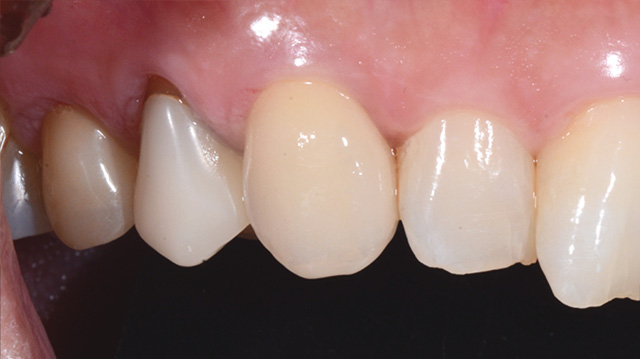

| 年代・性別 | 40代 女性 |

|---|---|

| 主訴 | 右上の犬歯の色が気になる |

| 治療回数 | 3回 |

| 治療期間 | 約1ヶ月 |

| 費用 | 仮歯 5,500円 ジルコニアクラウン 176,000円 |